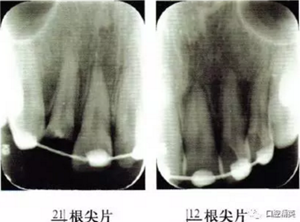

2冠根折,唇側(cè)斷端至齦下2mm,露髓,叩痛(+),不松,齦緣滲血;1冠折,未露髓,部分脫出,叩痛(+),松Ⅲ度,近中齦乳頭撕裂,長約1.5 cm;1挫入,切斷折斷,位于拉冠中部,叩診高調(diào)金屬音,不松,近中齦乳頭撕裂,長約1.5 cm;2見釉質(zhì)裂紋,叩痛(+),不松,齦緣滲血(圖1);以上牙齒X線均未見明顯根折線(圖2)。

圖2外傷牙鋼絲+釉質(zhì)粘接劑固定術(shù)后根尖片